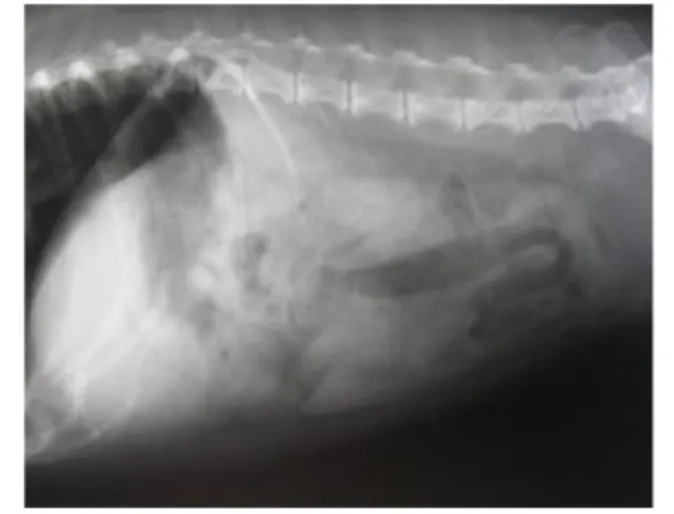

The diagnosis of GDV relies on the combination of a veterinarian’s physical exam and x-rays. On physical exam, a veterinarian may note evidence of dehydration or signs of shock (rapid heart rate, weak pulses, pale gums, and difficulty breathing). An enlarged, gas filled stomach can often be felt on abdominal palpation. Radiographs (x-rays) of a dog’s abdomen will confirm the presence of a dilated and twisted stomach as GDV has a characteristic appearance (“double bubble” or “Popeye’s arm”) on radiographs (compare Figures 1 and 2).

Figure 2. Normal abdominal radiograph.